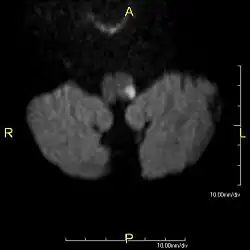

Das Wallenberg-Syndrom (synonym: Viesseaux-Wallenberg- und Wallenberg-Foix Syndrom oder auch Dorsolaterales Medulla-oblongata- oder Arteria-cerebellaris-inferior-posterior-Syndrom) entsteht durch einen Verschluss der Arteria cerebelli inferior posterior (PICA) oder der Arteria vertebralis. Als Folge davon kommt es zu einem Infarkt der dorsolateralen Medulla oblongata, die Teil des Hirnstamms ist.[1] Es ist eine seltene Form des Schlaganfalls. Die Symptome sind vielgestaltig entsprechend den jeweils betroffenen neurologischen Strukturen.

Es liegt ein Verschluss oder eine hochgradige Enge im Bereich der hinteren unteren Kleinhirnarterie (Arteria cerebelli inferior posterior) oder der Arteria vertebralis und ihrer Äste vor, die Teile des verlängerten Marks (Medulla oblongata) versorgen. Auslösend kann ebenfalls eine Hirnblutung in dieser Region sein. Es führt zu einem Infarkt am seitlichen Teil der Medulla oblongata, mit den dafür typischen Ausfallmustern. Häufigste betroffene Arterie ist die A. vertebralis.